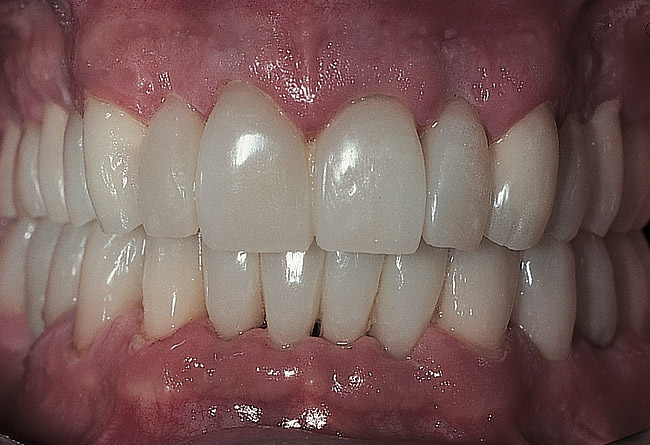

Figure 26  Final facial view of the maxillary and mandibular restorations.

Figure 26

Figure 27  Final facial view of the treatment.

Figure 27